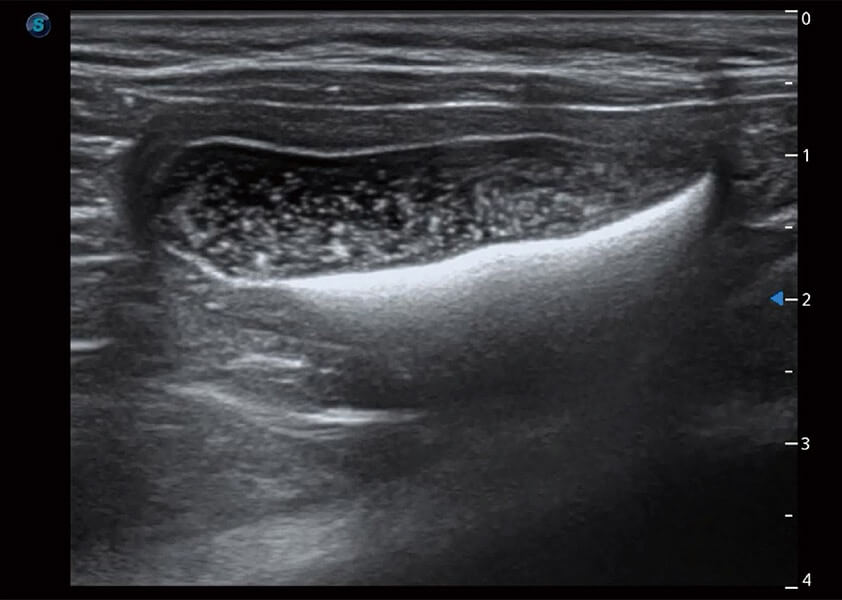

ProPet 60 作为一款高端台式动物超声设备,为动物医生的日常诊断提供了一系列贴合动物临床需求、解决临床实际问题的高级成像功能。凭借全系列高清探头,满足医生对腹部、心脏、生殖、浅表、肌骨等成像的所有需求,切实帮助您提升检查效率,提高诊断信心。

兽用彩色多普勒超声诊断系统